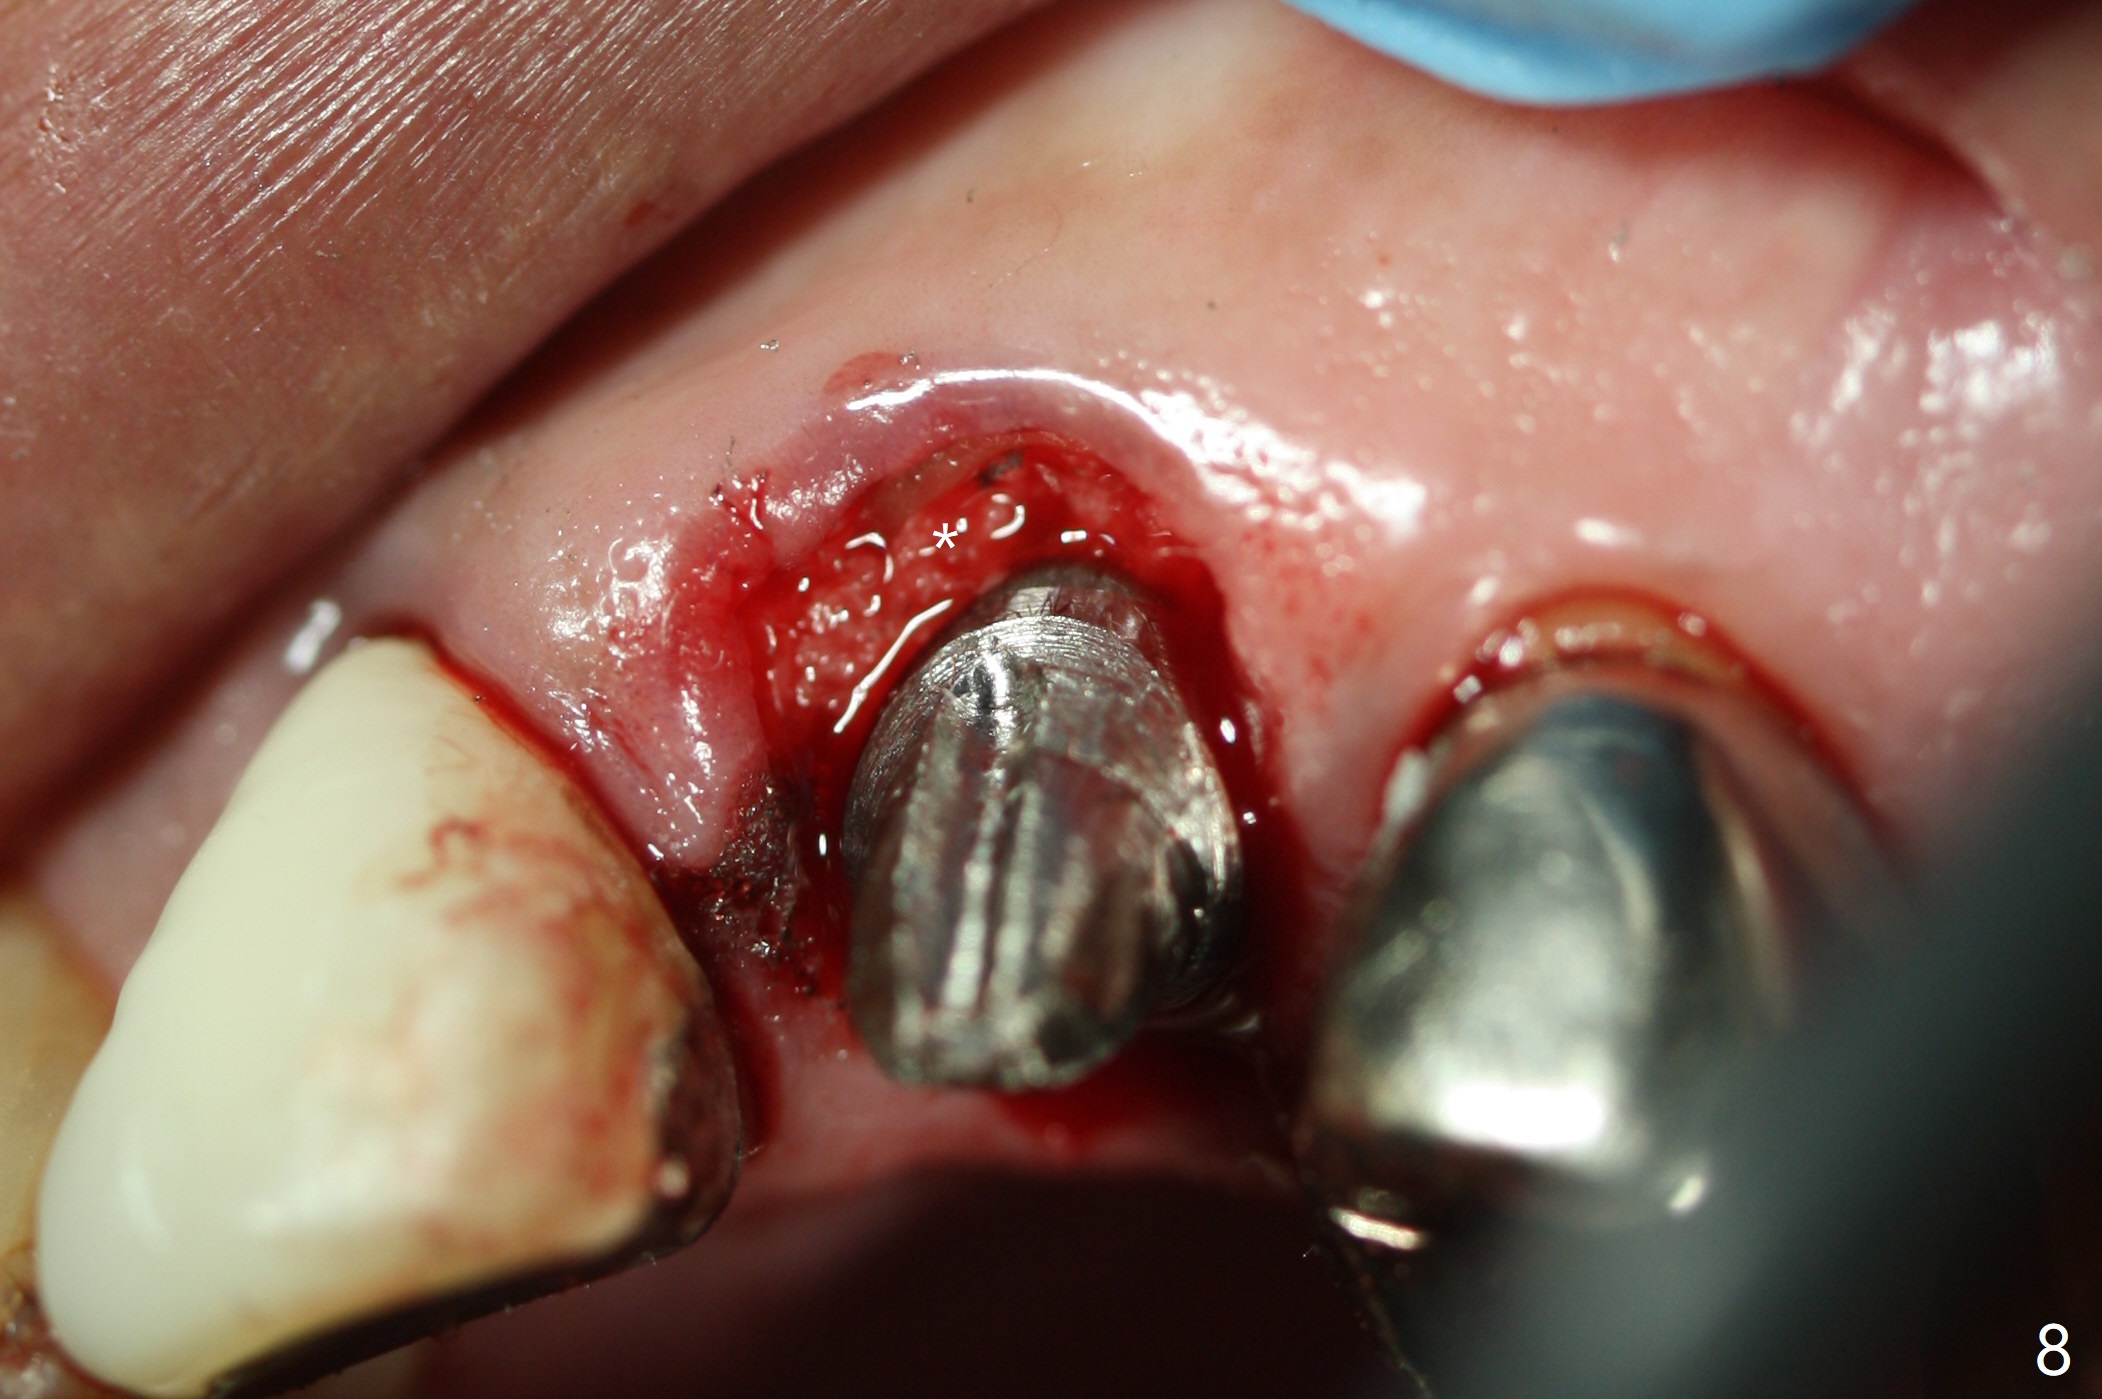

Extraction of the residual root at #11 (Fig.1) turns out to be difficult (Fig.2 (arrow: after use of small elevator). The tooth is sectioned (Fig.2 *); the palatal portion is removed, while the buccal one is trimmed until new moon-shaped and subgingival (Fig.3 * (gauze (G) packed in the socket while photo taking)). Initial osteotomy is 20 mm deep with nasal floor perforation (Fig.4). The subsequent depth is 17 mm (Fig.5). When a 5x17 mm tissue-level implant is placed (Fig.6,7; >60 Ncm), there is a gap between it and the socket shield (Fig.6 *). Gap-filling Vera Graft (Fig.8 *) also covers the shield prior to fabrication of an immediate provisional (Fig.9). There is no apparent bone loss 3.5 months postop (Fig.10). There is no buccal plate resorption 9 months postop (Fig.11). The implant is doing well 2 years postop (1 year 9 months post cementation, Fig.12).